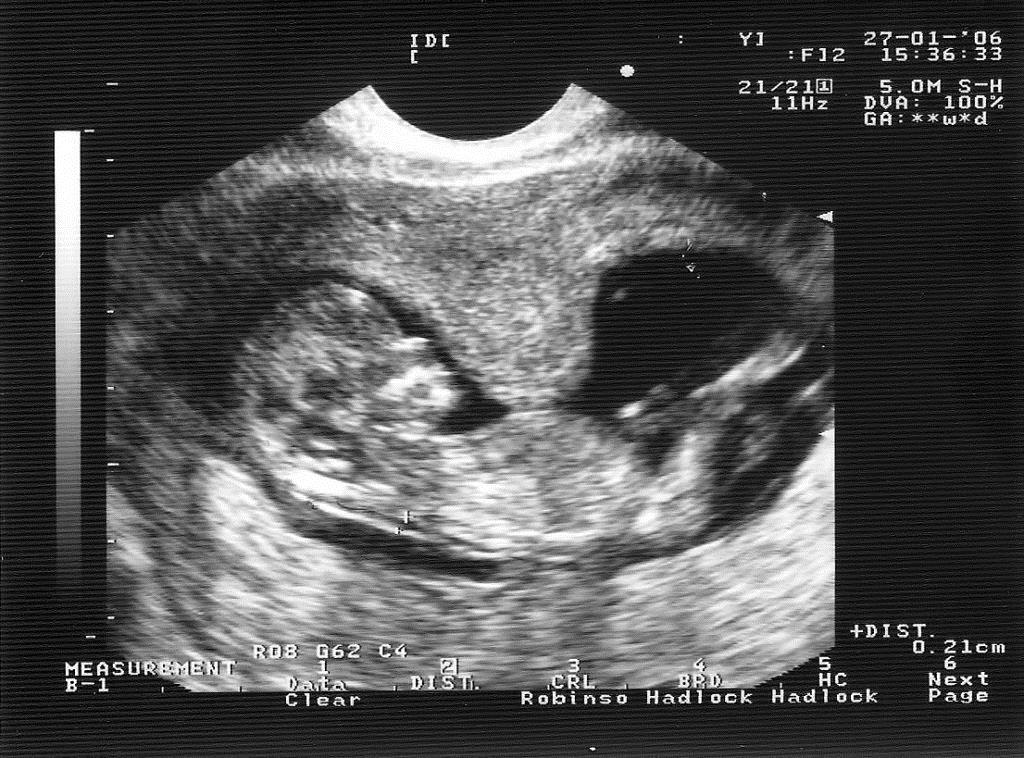

Как врачам удаётся определить тонус матки при беременности? Помимо самого распространённого метода пальпации, они прибегают к УЗИ-диагностике и кардиотокографии (КТГ).

Для начала разберемся, что означает этот непонятный диагноз. Тонус матки, или «гипертонус матки» чаще может возникать на ранних сроках беременности. Тонус матки во время беременности — это сокращения, которые появляются раньше предполагаемого срока родов. Ощущаются они как тянущие, ноющие боли внизу живота (похожее состояние в период менструаций), иногда боли в пояснице. Бывает, что женщина не обнаруживает никаких посторонних ощущений в своем организме, но при обследовании УЗИ показывает, что у нее гипертонус матки. Причины, вызывающие тонус матки, могут быть различными, начиная от недоразвитости половых органов и заканчивая волнением.

При осмотре живота и влагалищном исследовании тонус матки легко определяется, на УЗИ видны напряженные мышечные волокна. Есть и специальный аппарат для измерения силы сокращения миометрия при беременности, хотя широкого применения он не получил – и без того симптомы состояния слишком заметны.